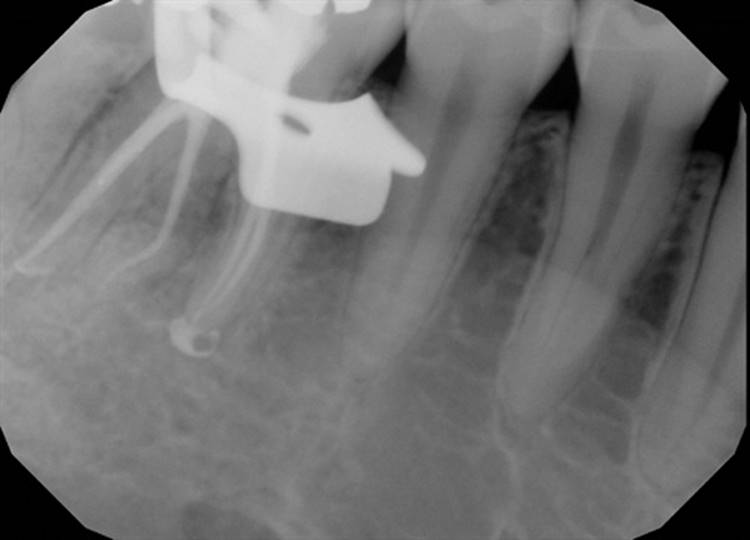

Forgive the sensor change from the first two cases to the last two. The good sensor broke and the back up isn’t as great.

EdgeFile® Cases